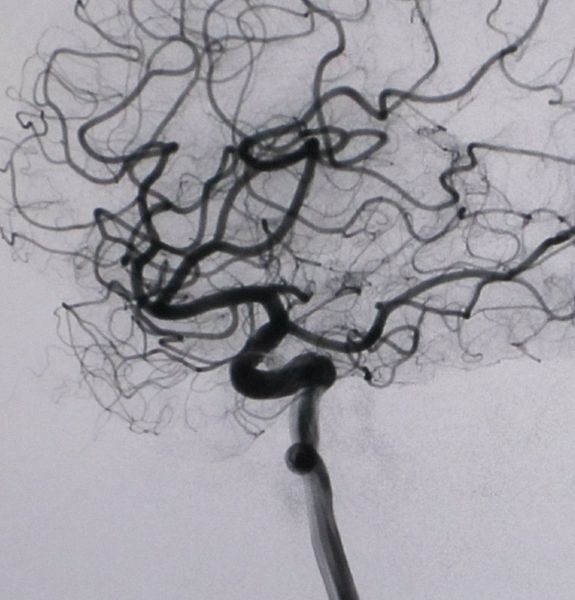

超選擇性血管造影主要用于顱內(nèi)腫瘤、膿腫、血腫、動脈瘤、動靜脈畸形、動脈阻塞性病變以及顱腦外傷后等的診斷和定位。近年來由于采用了數(shù)字減影血管造影(DSA)技術,血管造影已經(jīng)成為臨床的一種重要的診斷方法,尤其在介入治療中起著不可替代的作用。血管造影在頭頸部及中樞神經(jīng)系統(tǒng)疾病、心臟大血管疾病、及腫瘤和外周血管疾病的診斷和治療中都發(fā)揮著重要作用。

DSA的成像基本原理是將受檢部位沒有注入造影劑和注入造影劑后的血管造影X線熒光圖像,分別經(jīng)影像增強器增益后,再用高分辨率的電視攝像管掃描,將圖像分割成許多的小方格,做成矩陣化,形成由小方格中的像素所組成的視頻圖像,經(jīng)對數(shù)增幅和模/數(shù)轉(zhuǎn)換為不同數(shù)值的數(shù)字,形成數(shù)字圖像并分別存儲起來,然后輸入電子計算機處理并將兩幅圖像的數(shù)字信息相減,獲得的不同數(shù)值的差值信號,再經(jīng)對比度增強和數(shù)/模轉(zhuǎn)換成普通的模擬信號,獲得了去除骨骼、肌肉和其它軟組織,只留下單純血管影像的減影圖像,通過顯示器顯示出來。

通過DSA處理的圖像,使血管的影像更為清晰,在進行介入手術時更為安全。

DSA的成像方式分為靜脈注射數(shù)字減影血管造影(IVDSA)及動脈注射數(shù)字減影血管造影(IADSA)。前者指經(jīng)靜脈途徑置入導管或套管針注射對比劑行DSA檢查,可分為非選擇性IVDSA即導管置入外周靜脈或上腔靜脈內(nèi)顯示動脈影像,及選擇性IVDSA即導管頭置于受檢靜脈或心腔內(nèi)注射對比劑顯影。后者也可分為非選擇性動脈造影及選擇性動脈造影。非選擇性IADSA是指經(jīng)動脈途徑穿刺插管后,將導管頭端置于靶動脈的主動脈近端注射對比劑作順行顯影;而選擇性IADSA是指將導管頭端進一步深入到靶動脈的主干或主干的分支內(nèi)進行造影。